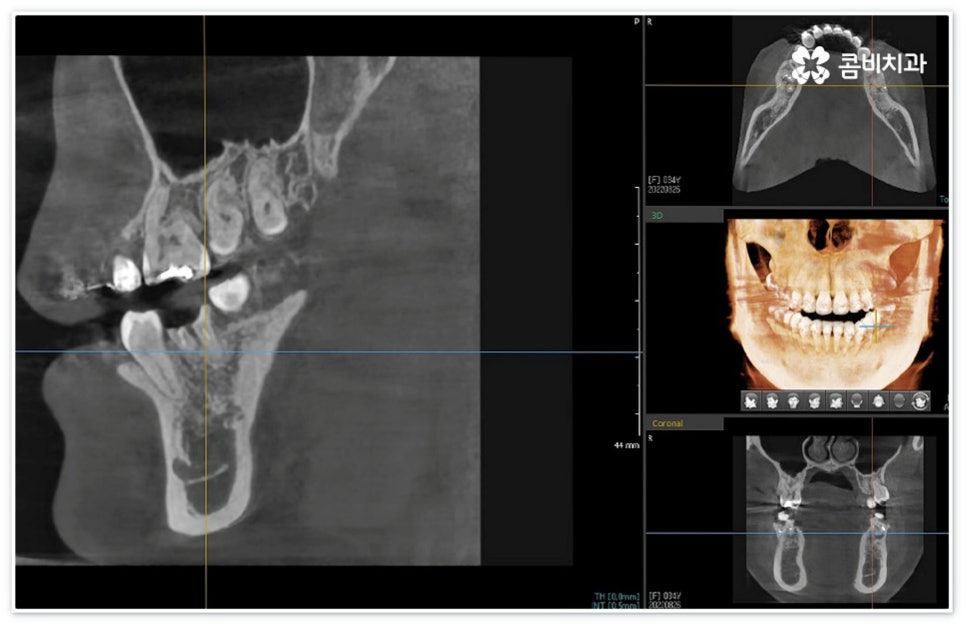

신경치료는 일견 간단해 보일 수 있으나 사람의 신경이 매우 얇고 또한 환자분들마다 신경관의 개수와 모양이 다 다르기 때문에 오염된 부위를 끝까지 깨끗하게 제거하기 위해서는 매우 섬세하고 뛰어난 기술력을 요하므로 다양한 임상 경험을 통해 풍부한 노하우를 가지고 있는 의료진과 함께 하실 필요가 있습니다.

혹여 미세한 부근관의 염증을 놓치거나 사후 외부 원인으로 2차 감염이 일어나는 경우 신경치료통증 이 오래 지속될 수 있으니 며칠이 지났음에도 욱신거림이 줄어들기는 커녕 점차 심해진다는 느낌이 있다면 다시 한 번 치과로 내원하셔서 꼼꼼하게 검진 후 필요한 치료를 받으시는 게 좋을 거예요. 상황에 따라 재신경치료를 진행해야 할 수도 있고 좀 더 지켜보면서 발치가 불가피하지는 않은지 신중하게 판단해야 할 수도 있는데요. 예를 들어 만약 신경치료통증 의 원인이 치료 전부터 치아 뿌리에 생겼던 미세한 균열 때문이라면 치료 받은 치아로 씹을 때 통증이 지속적으로 나타날 수 있고 재신경치료 등으로 이를 살릴 수 없으므로 이 통증이 일상생활에 큰 영향을 주지 않을 경우 최대한 사용하는 데까지 사용을 하다가 임플란트 치료를 권장 드리고 있으나 증상이 심할 경우 바로 발치를 해야 하며, 매우 낮은 확률이긴 하지만 신경관 내부 뿐 아니라 외부에도 세균 군집이 생겨 치아 뿌리 끝 염증이 나아지다가 다시 악화된 상황이라면 역시 약 처방 등으로 신경치료통증 을 잡을 수 없고 발치 후 임플란트 식립을 통해 치료해야 할 거예요.

이때 환자분들마다 상황이 다를 수 있는데 예를 들어 교정 치료 중 충치 치료 (신경 치료) 및 발치와 임플란트 식립과 같은 고난도의 치료들을 함께 진행해야 하는 복잡한 케이스의 경우에는 더욱 시술자의 숙련도가 중요하다고 할 수 있어요. 의료진의 자격증, 경력 사항, 분과별 협진 여부 등을 잘 알아 보시고 필요한 치료들을 모두 통합적으로 진행할 수 있는지, 또한 환자분들의 상황을 꼼꼼하게 살필 수 있는 3D CT 와 같은 정밀 검진 기계를 갖추고 있는지 등을 체크해 보신 후에 처음부터 끝까지 책임 진료하는 의료진과 철저한 케어 시스템을 갖추고 있는 치과를 선택하셔서 제 때 필요한 치료를 받으시길 권유드리고 있습니다.